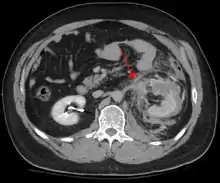

Blunt abdominal trauma

Blunt abdominal trauma (BAT) represents 75% of all blunt trauma and is the most common example of this injury.[4] 75% of BAT occurs in motor vehicle crashes,[5] in which rapid deceleration may propel the driver into the steering wheel, dashboard, or seatbelt,[6] causing contusions in less serious cases, or rupture of internal organs from briefly increased intraluminal pressure in the more serious, depending on the force applied. Initially, there may be few indications that serious internal abdominal injury has occurred, making assessment more challenging and requiring a high degree of clinical suspicion.[7]

When blunt abdominal trauma is complicated by 'internal injury,' the liver and spleen (see blunt splenic trauma) are most frequently involved, followed by the small intestine.[9]